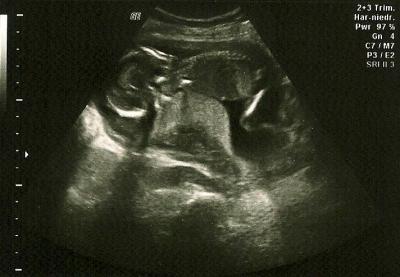

Hallo zusammen, ich war heute (SSW 15+5) nach laaangen drei Wochen auch wieder beim FA. Unser Spatz ist 10,73 cm groß (SSL) und es geht ihm blendend. Magen und Blase waren gefüllt. US-Bild ist im Anhang. Und unser Kleines hat sich sogar geoutet. Ein Mädchen! :-) Wir freuen uns sehr. Unser Großer bekommt also eine kleine Schwester. Der FA war sich ziemlich sicher, hat aber trotzdem gemeint, die Wände sollen wir noch nicht rosa streichen. ;-) LG und einen schönen Abend euch allen!

Bild zu FA-Bericht - Forum für April - Mamis